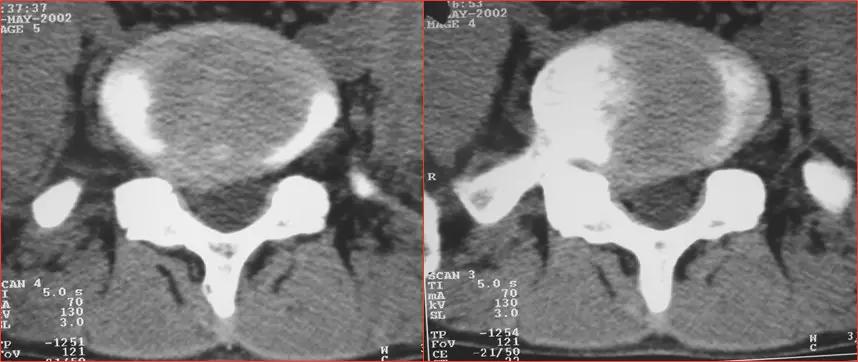

椎间盘突出右旁中央型

椎间盘突出左旁中央型

椎间盘膨出

椎间盘膨出伴右后突出